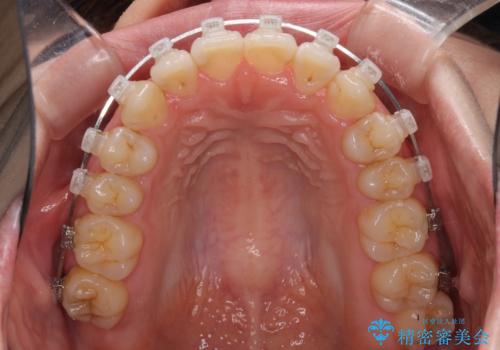

- 矯正装置

- クリアブラケット

目立たない装置と金属のワイヤーで矯正治療を行うこととしました。

1年半程度の期間を見込んでいましたが、上下の真ん中の位置をできる限り合わせるための調整に少し時間がかかってしまいました。